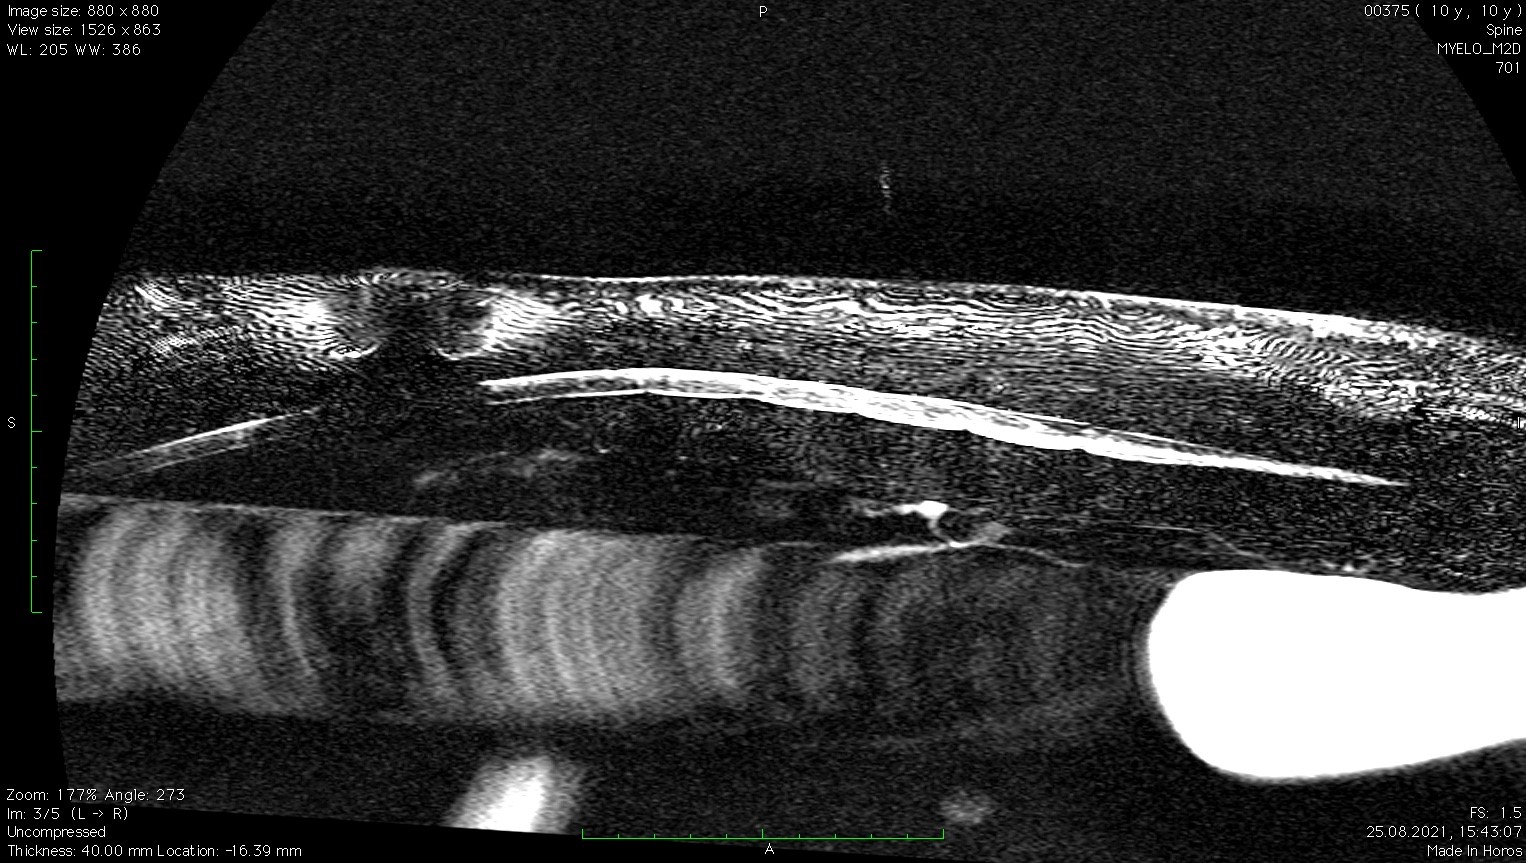

Заключение МРТ:

Признаки очагового образования с накоплением контраста в СМК на уровне Th10 (правая сторона) размером 2,2 х 2,3 см с поражением позвонка, окружающие ткани, выраженной компрессией СМ. С левой стороны на данном уровне отмечается артефакты. На уровне Th12-L2, L6-S1 отмечаются протрузии дисков.